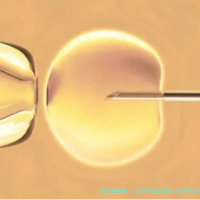

5bb囊胚已形成囊胚腔,内细胞群和外细胞群高度分化,各自承担不同发育任务。囊胚腔的形成标志着其处于高度分化状态,细胞间连接紧密,信号传导机制固定,不易发生分裂。

在培养囊胚的过程中,其实已经形成了内细胞群和外细胞群,随着不断发育,已经逐渐分化,所以移植成功后是不会再分裂的。

随着细胞的分裂和分化,遗传物质(DNA)也会进行精确的复制和分配。这种复制和分配过程受到严格的调控机制保障,以确保每个细胞都能获得完整且正确的遗传信息。5bb囊胚中,每个细胞的遗传物质都是相对稳定的,不易发生突变或重组。